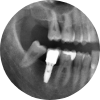

• 어금니 임플란트

씹는 힘을 지키는 치료,

어금니 임플란트 포항미르치과병원이 완성합니다.

어금니는 강한 저작력을 필요로 하는 치아로,

음식물을 잘게 부수고 소화를 돕는 중요한 역할을 합니다.

따라서 어금니를 상실했을 경우, 가능한 빠른 시기에 기능을 회복하는 것이 매우 중요합니다.

포항미르치과병원은 어금니 상실 시, 빠른 기능 회복은 물론 안정적인 교합까지 고려한 정밀한 임플란트 치료를 제공합니다.

보이지 않는 부분까지 완성도 있게, 기능 중심의 치료 철학을 지켜갑니다.